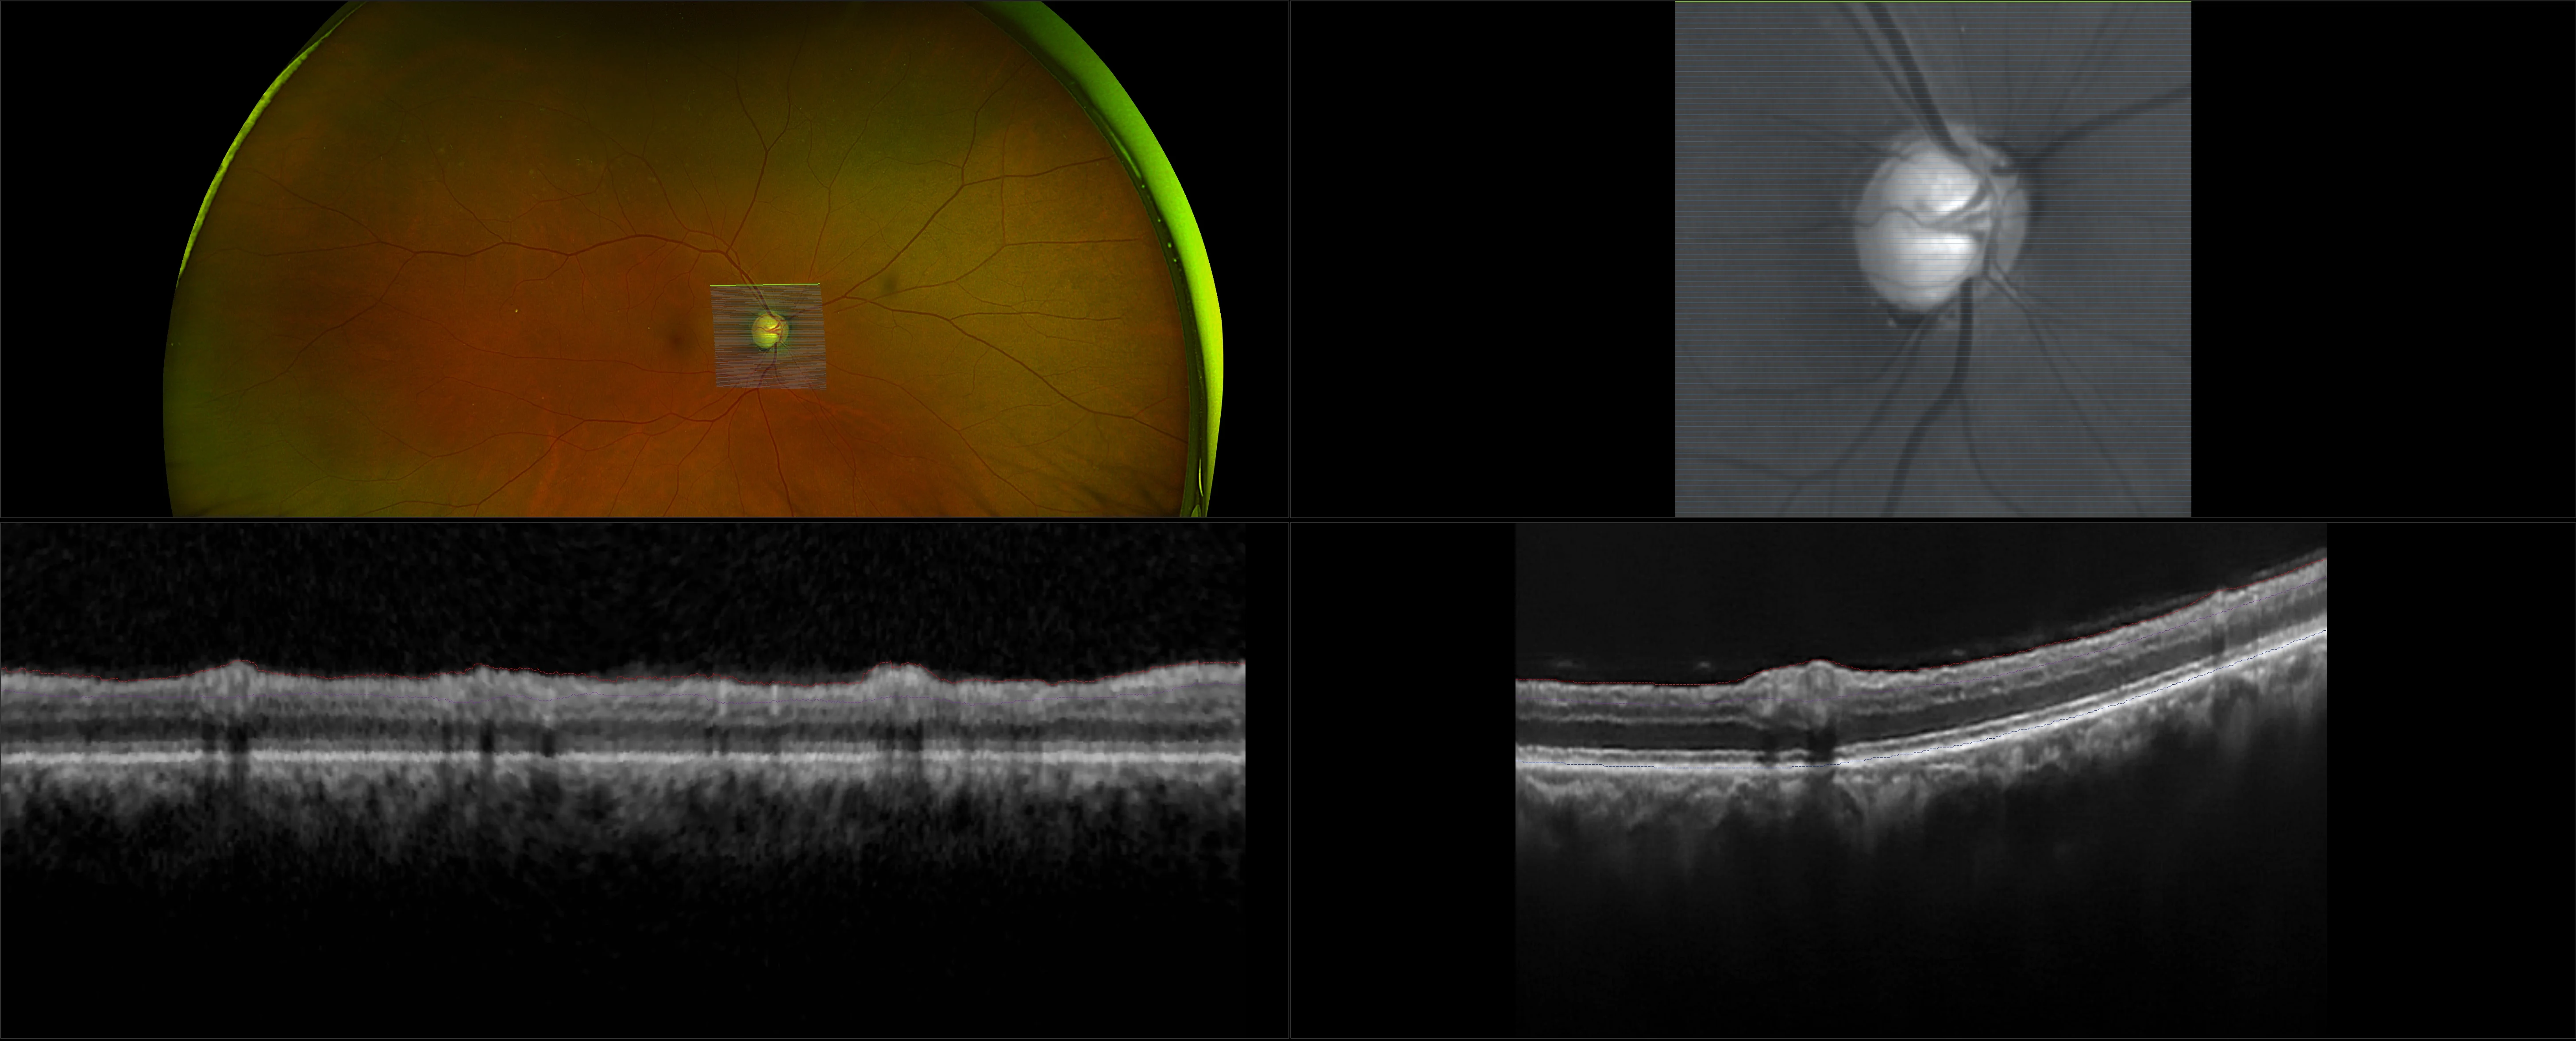

Glaucoma is a group of eye diseases that progress gradually, stealing sight, without showing symptoms. The word ‘glaucoma’ is actually an umbrella term for a group of eye diseases that damage the delicate fibers of the optic nerve. Damage is often the result of high fluid pressure inside the eye. Glaucoma can affect people of all ages but is most prevalent in middle-aged adults and the elderly. Results from published clinical studies suggest that optomap may play an essential role in glaucoma management. Optos devices capture and provide details needed for glaucoma exams such as segmentation and reference data specifically found with the MonacoPro device, while simultaneously delivering an integrated view to the eye.